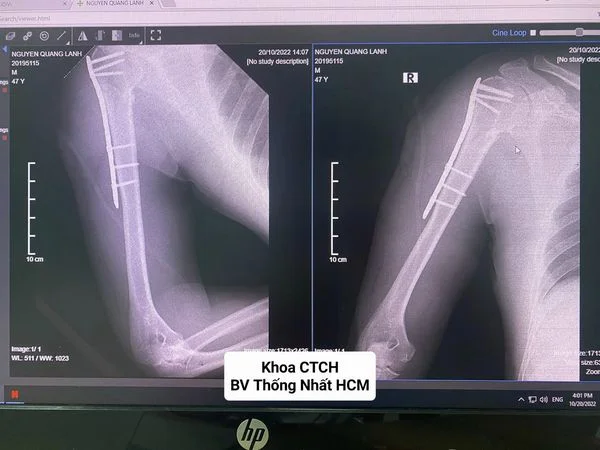

PHẪU THUẬT KẾT HỢP XƯƠNG ÍT XÂM LẤN (MIPO) LÀ GÌ?

Phẫu thuật kết hợp xương ít xâm lấn là kỹ thuật cố định những mảnh xương gãy bằng các thiết bị cơ học như nẹp vít, đinh nội tủy mà không phải mở rộng toàn...